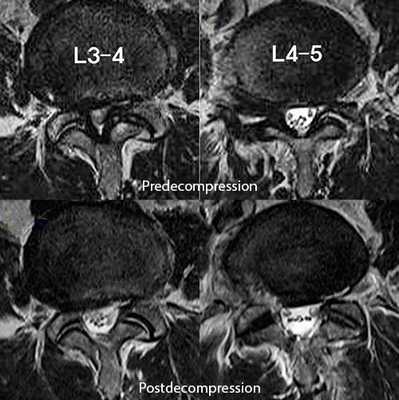

![На МРТ поясничного отдела позвоночника показан стеноз позвоночного канала и состояние после операции эндоскопической декомпрессии на уровнях L3-L4 и L4-L5.]()

На МРТ поясничного отдела позвоночника показан стеноз позвоночного канала и состояние после операции эндоскопической декомпрессии на уровнях L3-L4 и L4-L5.

Иногда при стенозе позвоночного канала бывает целесообразно разделить операцию на два этапа. На первом этапе выполняется декомпрессия наиболее страдающих корешков спинного мозга, проводится курс интенсивной вазоактивной и нейростимулирующей терапии. И, если не достигнуто улучшение и облегчение состояния больного, можно предложить второй этап операции — более широкую декомпрессию (двустороннюю гемиламинэктомию) и создание дополнительных резервных пространств при стенозе позвоночного канала.